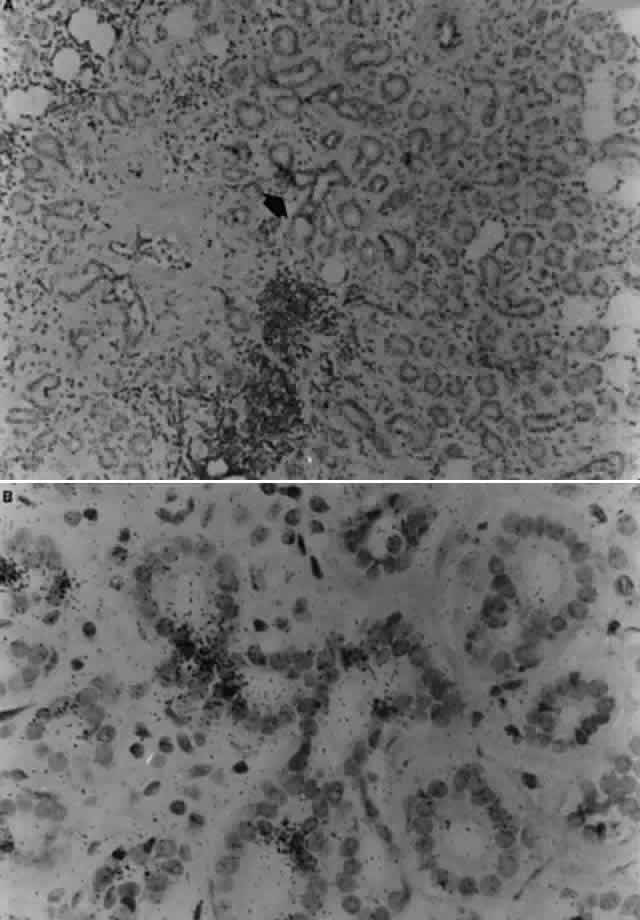

Reported studies using PCR to detect EBV genomes in normal and Sjögren's syndrome lacrimal gland biopsies did not indicate the infected cell types within the lacrimal gland, nor did they determine if the amplified EBV DNA sequences were from latent EBV genomes or replicating virus. The results of studies reported by Pflugfelder and associates82,83 suggest that EBV may persist in the normal human lacrimal gland in a latent nonpathologic state. The cellular site and state of genome expression in normal human lacrimal glands persistently infected with EBV appears to be similar to that reported to occur in normal salivary glands (Fig. 6).25 In contrast, the results of studies using in situ DNA hybridization and immunohistochemical techniques to evaluate Sjögren's syndrome lacrimal glands for EBV infection indicate that there may be a much more extensive infection of ductal epithelia than observed in normal lacrimal glands, as well as infection of mononuclear cells in areas of B-cell lymphoproliferation. EBV antigens were detected in both lymphocytes and epithelial cells in Sjögren's syndrome lacrimal glands; however, the pattern of antigen expression differs in these two cell types. EBV antigens associated with immortalization of B cells, LMP-1, and EBNA-2 were detected in mononuclear cells in areas of B-cell lymphoproliferation. B cells in Sjögren's syndrome lacrimal glands expressing EBV latent infection cycle antigens also expressed ICAM-1, CD-23 and CD-21, the typical repertoire of antigens upregulated by EBV following immortalization of B cells. Based on these findings, it appears that EBV infection of B lymphocytes in Sjögren's syndrome lacrimal glands may be responsible for the B-cell lymphoproliferation observed in these glands. In contrast, epithelial cells located in areas of lymphoproliferation in Sjögren's syndrome lacrimal gland strongly expressed early (EA-R) and late (VCA) EBV lytic-cycle antigens. These findings suggest that a lytic EBV infection may occur in epithelial cells in Sjögren's syndrome lacrimal glands. Because EBV genomes have been detected in the majority (80%) of tear specimens obtained from primary Sjögren's syndrome patients, it is possible that EBV-infected ductal epithelium may be the source of the virus shed into the tears. Similar to other EBV-associated neoplasias, a lymphoepithelial pathology is frequently observed in Sjögren's syndrome lacrimal gland biopsies.83 The lymphoepithelial pathology in Sjögren's syndrome lacrimal glands differs from nasopharyngeal carcinoma in that lymphoproliferation surrounding epithelium in Sjögren's syndrome lacrimal glands consists predominantly of B lymphocytes, whereas T cells typically surround epithelia in nasopharyngeal carcinoma.84 In lacrimal gland lobules with mild inflammation occurring in patients with Sjögren's syndrome, the B-cell lymphoproliferation is observed surrounding ducts in the center of the lobule and normal-appearing acini may still be present in the peripheral lobule. In more severely affected glands, the lymphoproliferation replaces all secretory acini and the ducts in areas of B-cell lymphoproliferation have an abnormal morphology and pattern of cytokeratin expression.83

Fig. 6. A. Normal lacrimal gland biopsy showing hybridization signals for EBV DNA in intralobular duct epithelia indicated by black arrow (X 100 original magnification). B. Magnified photomicrograph of EBV-positive ductal epithelia in upper figure (X 400 original magnification).